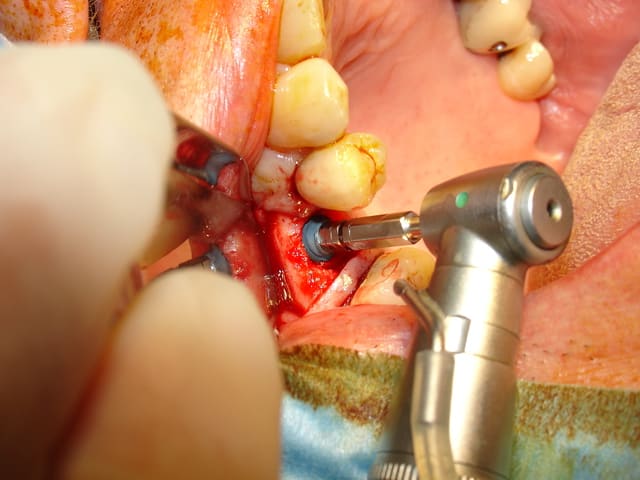

Il existe 2 solutions pour le retirer la piezzo ou le trépan.

J'ai donc choisi cette dernière solution très rapide.

Je vous laisse regardé les images.